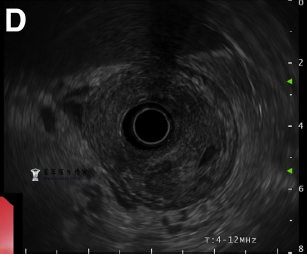

内窥镜超声检查显示胃窦壁周围增厚达20mm,且粘膜下层内存在不均匀低回声区(图D)。

蜂窝织炎性胃炎患者的内窥镜超声检查通常表现为胃部弥漫性增厚,可存在于其他粘膜下病变(如类癌或平滑肌瘤)患者中不常见的粘膜下壁层低回声。